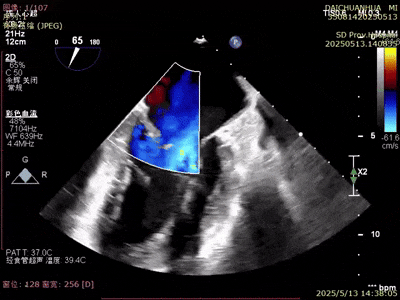

術(shù)前超聲

A3脫垂連枷(脫垂高度9mm,連枷高度:7mm),反流等級(jí)MR 4+(反流寬度11mm),有效瓣環(huán)面積MVA約6.3cm²。前瓣葉長(zhǎng)度23,后瓣葉長(zhǎng)度14.5mm,瓣環(huán)直徑AP 29mm。